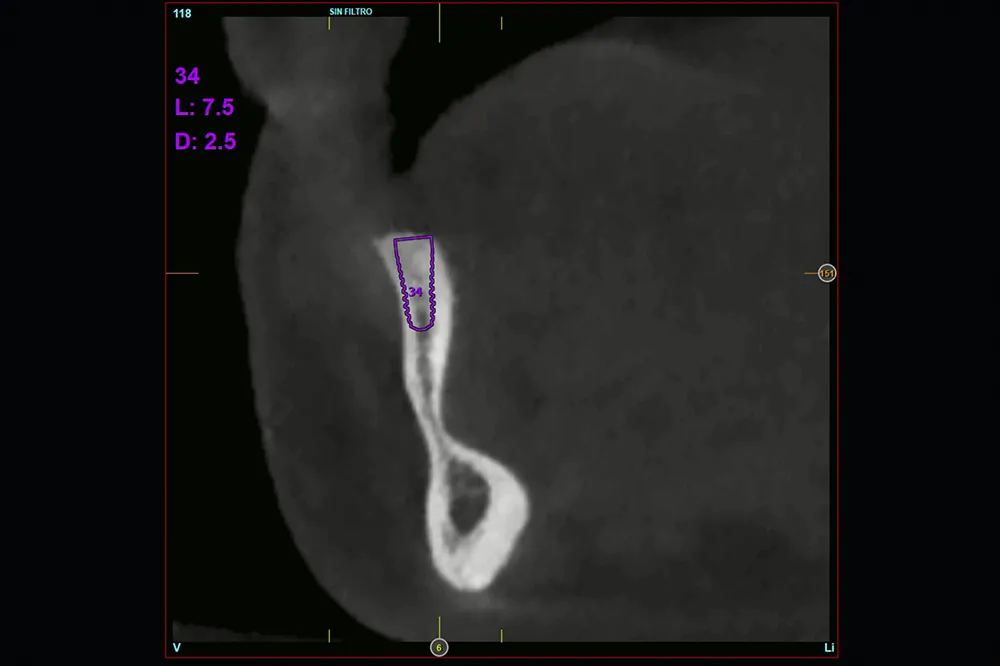

Figuras 8-11. Cortes seccionales del cone-beam de planificación del tercer cuadrante, donde podemos observar la extrema atrofia horizontal que encontramos en algunas localizaciones, con menos de 4 mm de anchura. Por ello, se planifican implantes de 2,5 mm en todo el cuadrante.